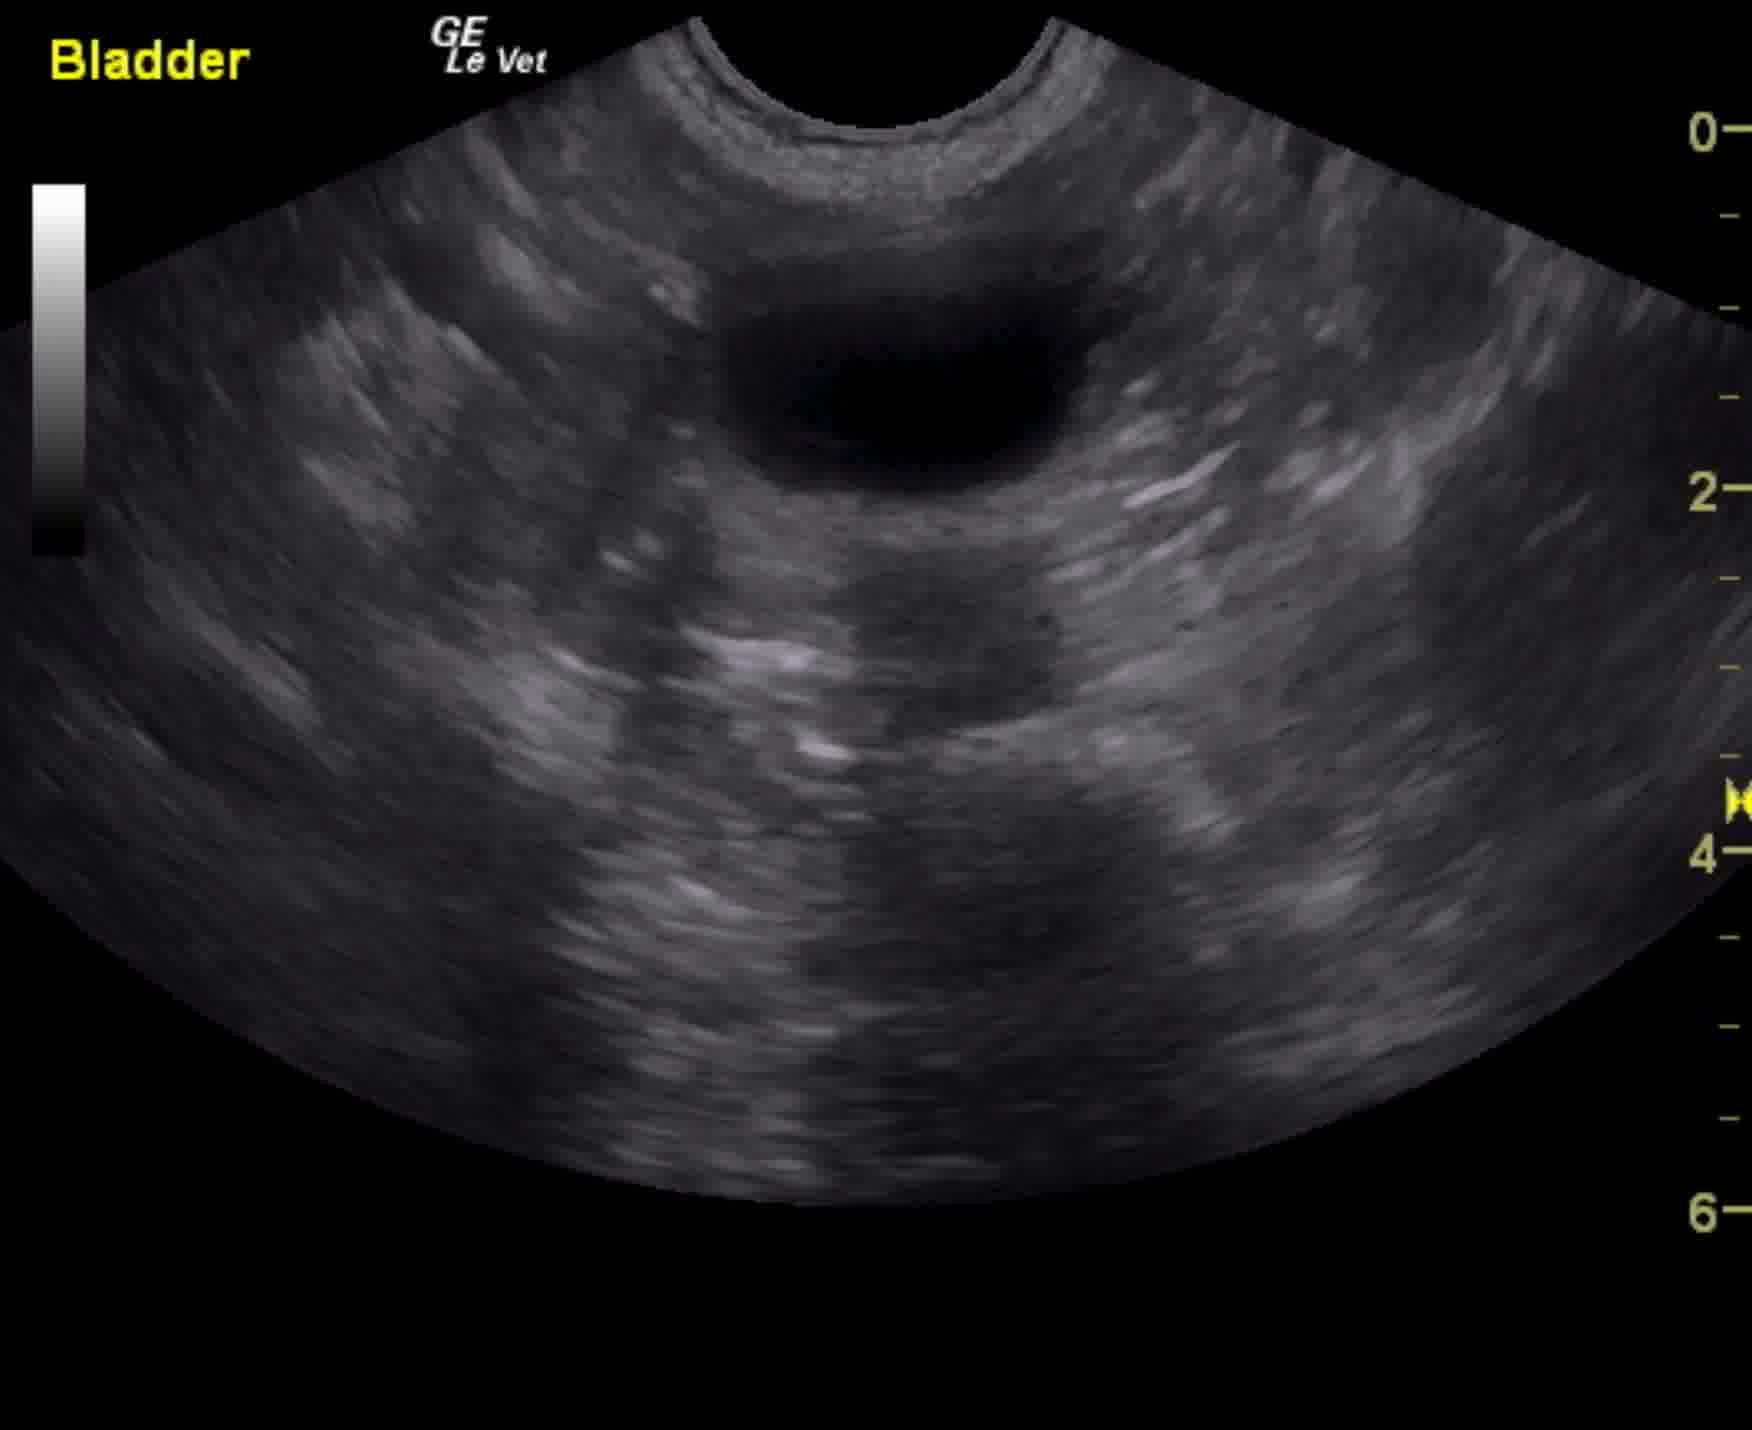

The urinary bladder presented minor mural thickening with slight, micropolypoid changes.